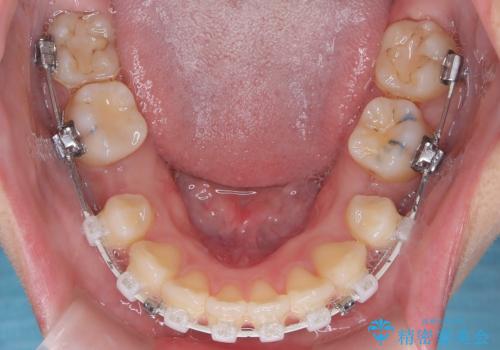

今回の矯正治療では、口元の突出感を解消するためのスペースを確保するため、計画通り上下左右4本の小臼歯を抜歯しました。装置には、確実な歯の移動と細やかな調整が可能なワイヤー矯正を採用。抜歯によってできたスペースを最大限に利用し、前歯を奥へ、そして垂直的に慎重に移動させました。

- 口元が出ていること(突出感)を気にされ、これを下げたいという主訴でご来院されました。精密な検査の結果、前歯を大きく後退させ、口元を改善するためには、スペースの確保が不可欠と診断しました。そこで、上下左右の第一小臼歯(4番目の歯)を計4本抜歯し、そのスペースを利用して前歯全体を奥へ移動させる抜歯矯正の治療計画を立案。確実な歯の移動を実現するため、ワイヤー矯正装置を使用しました。